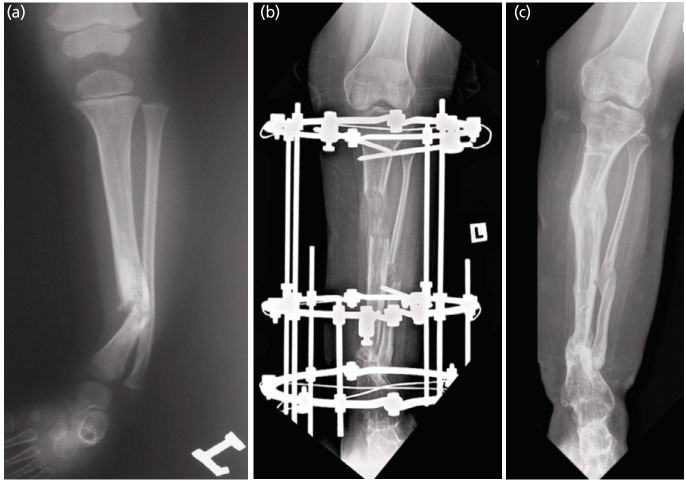

Results: Twelve patients (13 tibiae) were reviewed with an average follow-up of 14.5 years (range 3.1-24.0 years). Nine (69.2%) tibiae underwent intramedullary (IM) rodding; two (15.4%) were stabilised with the Ilizarov external fixator (IEF) + IM rod; and two other (15.4%) tibiae with the IEF only. Primary union was achieved in 5 (38.5%) tibiae, but refractures occurred in two tibiae (40%), lowering the overall success rate to 23.1%. Fixation with IM rodding alone led to a low primary union rate (22.2%) but combining it with IEF avoided refracture. Seven (53.8%) tibiae reached skeletal maturity and had a union at 12.6 years (7.5-17.4 years), after an average of 3 surgical procedures. Four (57.1%) were Johnston Grade I, and 3 (42.9%) were Grade II. Four (57.1%) tibiae had residual tibial valgus, two (28.6%) tibial varus, four (57.1%) procurvatum and one (14.3%) recurvatum. The average LLD was 3.9cm (2-10cm).

Conclusion: Intramedullary rodding alone is ineffective for producing a bony union but combining it with IEF minimise the refracture rate. The chances of union increased with age, but residual deformity and shortening are an ongoing challenge.